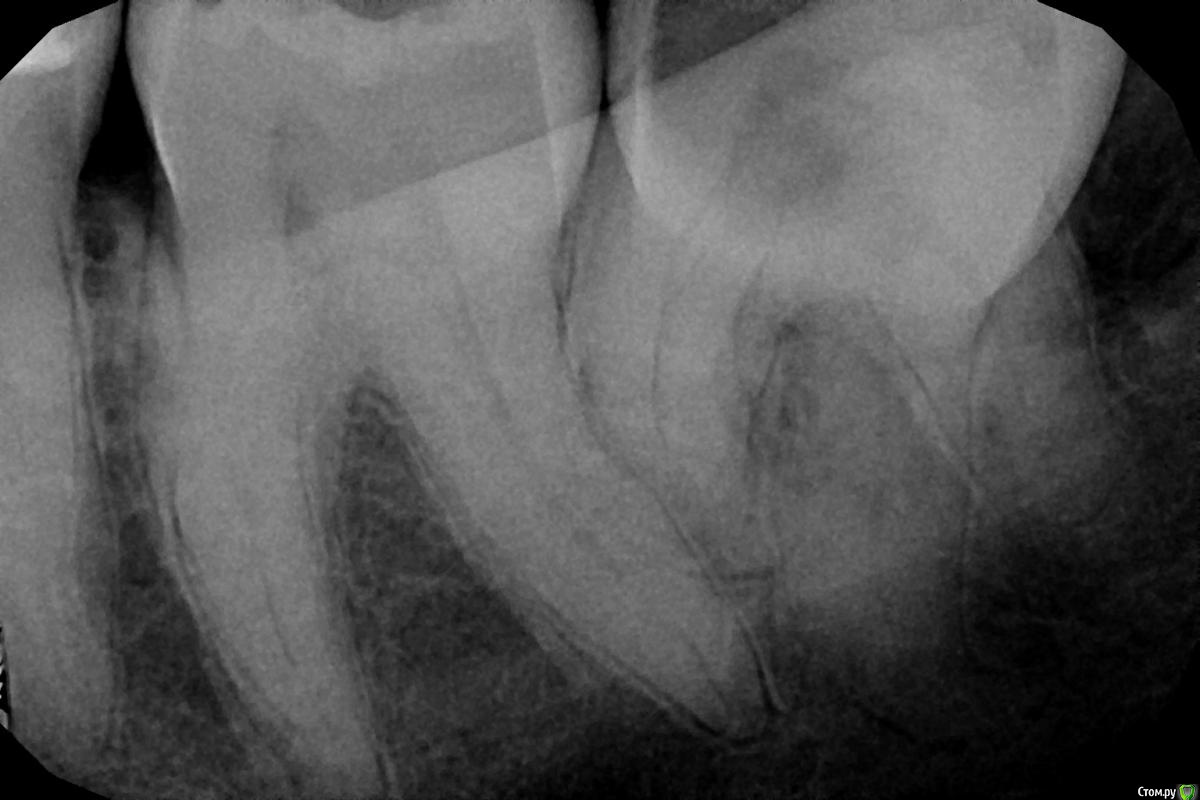

SDC Опубликовано 17 февраля, 2015 Поделиться Опубликовано 17 февраля, 2015 http://s017.radikal.ru/i413/1502/2c/e24b3e24a808.jpg http://s010.radikal.ru/i313/1502/78/64de26d778ee.jpg 7 Ссылка на комментарий